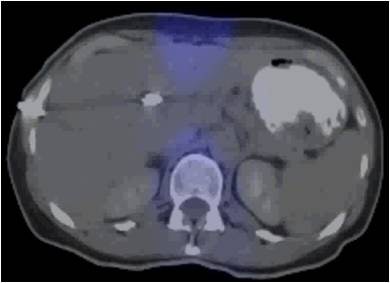

| The 3D VIBE MR image (above) shows the difference in data acquired compared to CT with stereotactic body radiation therapy (below). All images courtesy of Dr. John Mikell. |

![]() |